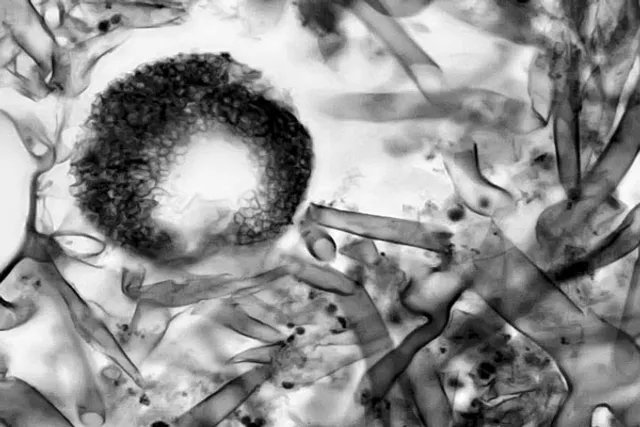

According to Malcolm Richardson, Consultant Clinical Scientist in Medical Mycology at University of Manchester, the term ‘black fungus’ is totally inappropriate. He was recently quoted by Medical News Today saying that the agents of mucormycosis are rather transparent. The term is rather fitting for fungi dematiaceous that contain melanin in their cell walls.

The fungi causing mucormycosis generally block blood flow in an infected host’s body. The blockage eventually leads to death of the tissue thus giving a black colouration to the skin covering the infected part.